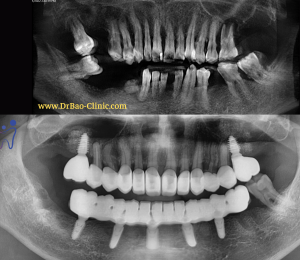

Bạn T.T.D.T (24 tuổi) đến nha khoa với mong muốn trồng lại răng cửa bị mất từ lâu do tai nạn

- Răng tạm bằng PMMA tạo hình nướu, sử dụng trong 4 – 6 tháng

- Lấy dấu làm phục hình sau cùng bằng sứ zirconia nâng đỡ trên implant

****Bước 2: (4 tháng sau)

Sau khi tháo phục hình tạm, nướu bệnh nhân đã được tạo hình phồng ra như răng thật – Giúp đảm bảo vệ sinh và thẩm mỹ khi cười.

Lấy dấu làm phục hình sau cùng bằng sứ zirconia

Răng sứ được hoàn tất tại labo